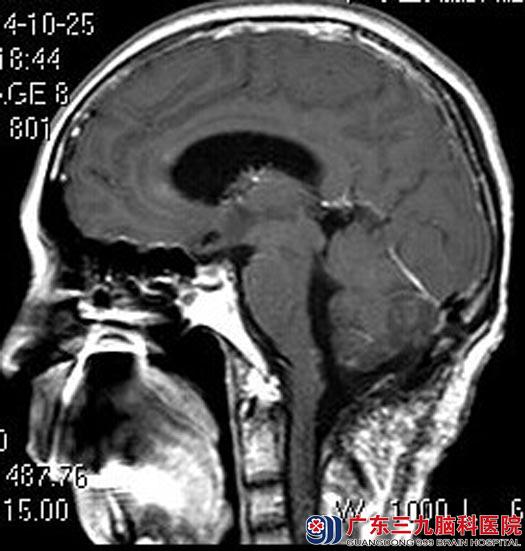

广东三九脑科医院头颅MR检查提示:四脑室内及右侧侧孔区桥小脑区团片状异常信号,大小约48.8 mm×37.2 mm×50.6mm,肿瘤与脑干粘连。

手术前